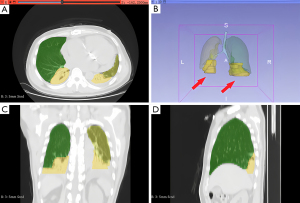

Three-dimensional (3D) Slicer lung CT analysis

Chest CT images were analyzed using the 3D Slicer platform (version 4.10.2, https://www.slicer.org) with the “Lung CT Segmenter” and “Lung CT Analyzer” modules (14,15). The “Lung CT Segmenter” module was employed to delineate lung boundaries, ensuring precise segmentation of lung tissue. The volumes of lung regions were classified into four categories based on their radiological appearance: emphysema, inflated, infiltration, and collapse. These categories were subsequently analyzed using the “Lung CT Analyzer” module. The total CT score was calculated by multiplying the percentage of each volume category by its respective weight and summing the results. This scoring system provided an objective assessment of the severity and distribution of PCA the lung parenchyma.

Chest CT scans were analyzed using the 3D Slicer software, which segmented the lungs into regions categorized as emphysema, inflated, infiltration, and collapse. A weighted CT score was calculated based on the volume of each category. These detailed segmentations were manually delineated and reconstructed in 3D, providing comprehensive visualizations of PCA (Figure 3).